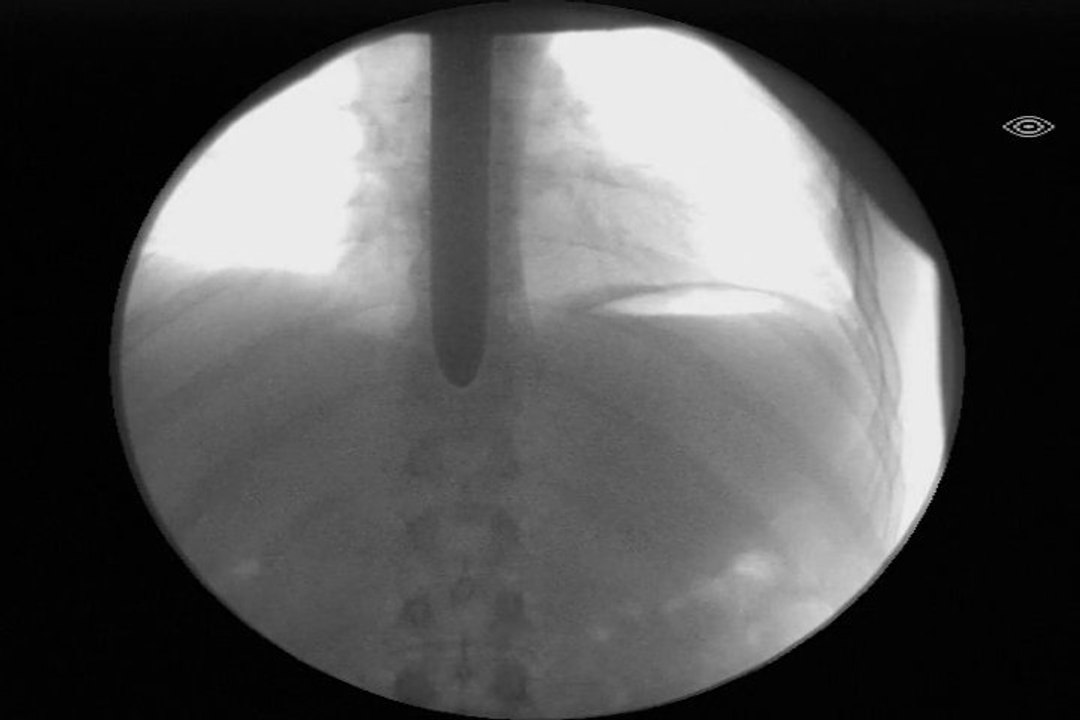

Sword Swallower Dan Meyer<br />16 Got Talents 40 World records 60 countries<br /><br />https://CuttingEdgeInnertainment.com<br />https://instagram.com/DanMeyerswords<br />https://tiktok.com/@danmeyers...